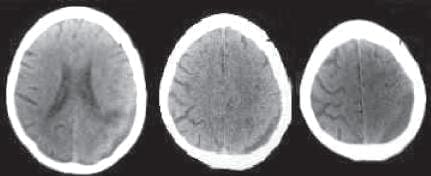

Ingresa al servicio de urgencias con un INR de 3.8 y un Glasgow de 5/15. Se toma un TAC de cráneo simple donde se observa un hematoma subdural agudo (imagen No. 1). Se practicó una craneotomía frontoparietal izquierda con la evacuación del hematoma subdural.

El paciente progresivamente manifiesta síntomas persistentes de cefalea holocraneana, se realiza un nuevo control radiológico al mes del cuadro agudo subdural, y se observa en las imágenes, la formación de un hematoma subdural crónico izquierdo (imagen No. 2). Los familiares refieren que el paciente duerme preferencialmente sobre el lado derecho.

Los controles radiológicos muestran la absorción progresiva del hematoma (imagen No. 3), hasta el último control 3 meses después con la absorción completa, se visualiza también en las imágenes la encefalomalacia producida por la lesión vascular en el territorio frontoparietal izquierdo (imagen No. 4).

Imagen No. 1. TAC de cráneo simple con hematoma subdural agudo izquierdo.

Imagen No. 2. Resonancia Magnética cerebral 4 semanas después. Se observa un hematoma subdural crónico izquierdo.

Imagen No. 3. TAC de cráneo simple 2 meses después. Se observa la absorción progresiva del hematoma subdural crónico izquierdo.

Imagen No. 4. TAC de graneo simple sin hematoma subdural. Se modificaron las imágenes para eliminar el nombre y los datos del paciente.